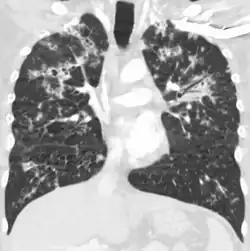

A case of miliary tuberculosis in an 82-year-old woman:

CT, 16 days after onset, showing extensive pulmonary parenchymal involvement consisting of irregular septal thickenings with ground-glass areas and centrilobular nodules with a peri-lymphatic distribution -